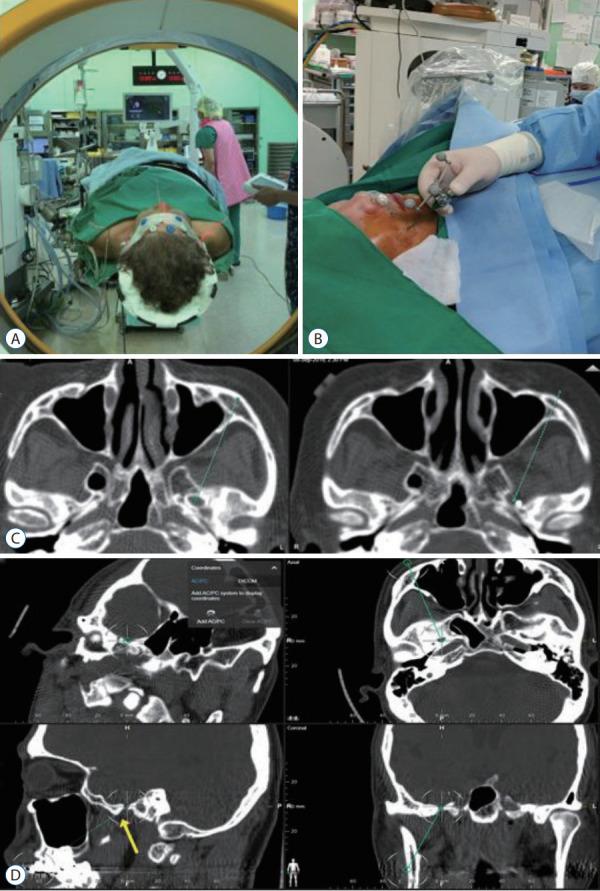

Percutaneous Procedures for Trigeminal Neuralgia.

Microvascular decompression is the gold standard for the treatment of trigeminal neuralgia (TN). However, percutaneous techniques still play a role in treating patients with TN and offer several important advantages and efficiency in obtaining immediate pain relief, which is also durable in a less invasive and safe manner. Patients' preference for a less invasive method can influence the procedure they will undergo. Neurovascular conflict is not always a prerequisite for patients with TN. In addition, recurrence and failure of the previous procedure can influence the decision to follow the treatment. Therefore, indications for percutaneous procedures for TN persist when patients experience idiopathic and episodic sharp shooting pain. In this review, we provide an overview of percutaneous procedures for TN and its outcome and complication.

微血管减压术是治疗三叉神经痛(TN)的金标准。然而,经皮技术在治疗TN患者中仍发挥着作用,并且在获得即时疼痛缓解方面具有几个重要优势和效率,而且以微创和安全的方式实现的疼痛缓解也是持久的。患者对微创方法的偏好会影响他们将接受的手术。神经血管冲突并非TN患者的必要条件。此外,先前手术的复发和失败会影响后续治疗的决策。因此,当患者出现特发性发作性剧痛时,TN经皮手术的适应证仍然存在。在本综述中,我们概述了TN的经皮手术及其结果和并发症。